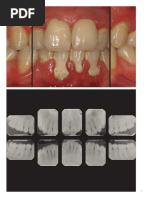

TABLA 2Marco para la estadificación y clasificación de la periodontitis.

TABLA 3Etapa de periodontitis: consulte el texto y el apéndice A (en líneaRevista de Periodoncia Clínica) para explicación

Etapa de la periodontitis (Tabla 3)

En la actualidad se dispone de datos relevantes para evaluar las dos dimensiones del

[Link] suficientemente simple como para ser clínicamente aplicable pero no proceso de estadificación: severidad y complejidad. Estos pueden evaluarse en cada

simplista: el conocimiento adicional ha distinguido dimensiones de la caso individual en el momento del diagnóstico mediante datos anamnésicos, clínicos y

periodontitis, como la complejidad del manejo del caso para brindar el de imagen adecuados.

mejor nivel de atención. La puntuación de gravedad se basa principalmente en el CAL interdental en

[Link] para poder respaldar una comunicación efectiva entre todas reconocimiento de la baja especificidad de la pérdida ósea tanto de las bolsas como de

las partes interesadas. la pérdida ósea marginal, aunque la pérdida ósea marginal también se incluye como

[Link] para una amplia gama de personas en formación y comprendido por un descriptor adicional. Sigue el marco general de puntuaciones anteriores basadas

miembros del equipo de atención de salud bucal de todo el mundo. en la gravedad y se asigna en función del diente más afectado de la dentición. Para la

puntuación sólo se utiliza la pérdida de inserción atribuible a la periodontitis.